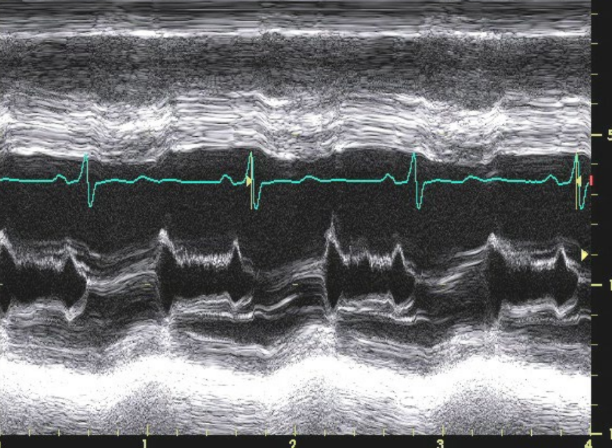

CW Doppler

Density proportional to what

Density of signal increase as what increase

how does Mild regurgitation show up

how does Severe Regurgitation show up

Sensity proportional to RBCās

Density of signal increase as RV increase

Mild R

Faint Doppler signal

Difficult to obtain

Severe R

Dense Doppler signal

Shape of CW Doppler reflects?

Severe AR may become asymmetrical

reflecting

Shape of CW Doppler reflects pressure

changes

reflecting rapid equalization of pressure